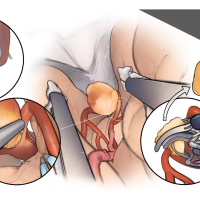

FEN2022シリーズ